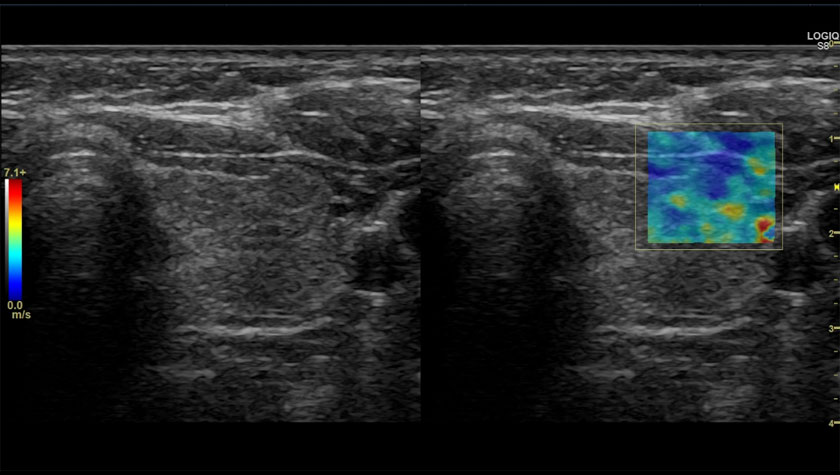

Щитовидная железа, 2D-эластография сдвиговой волны

Эластография молочной железы, датчик ML-6-15-D

- Elastography Quantification — Количественная эластография;

- Elastography — Эластография;